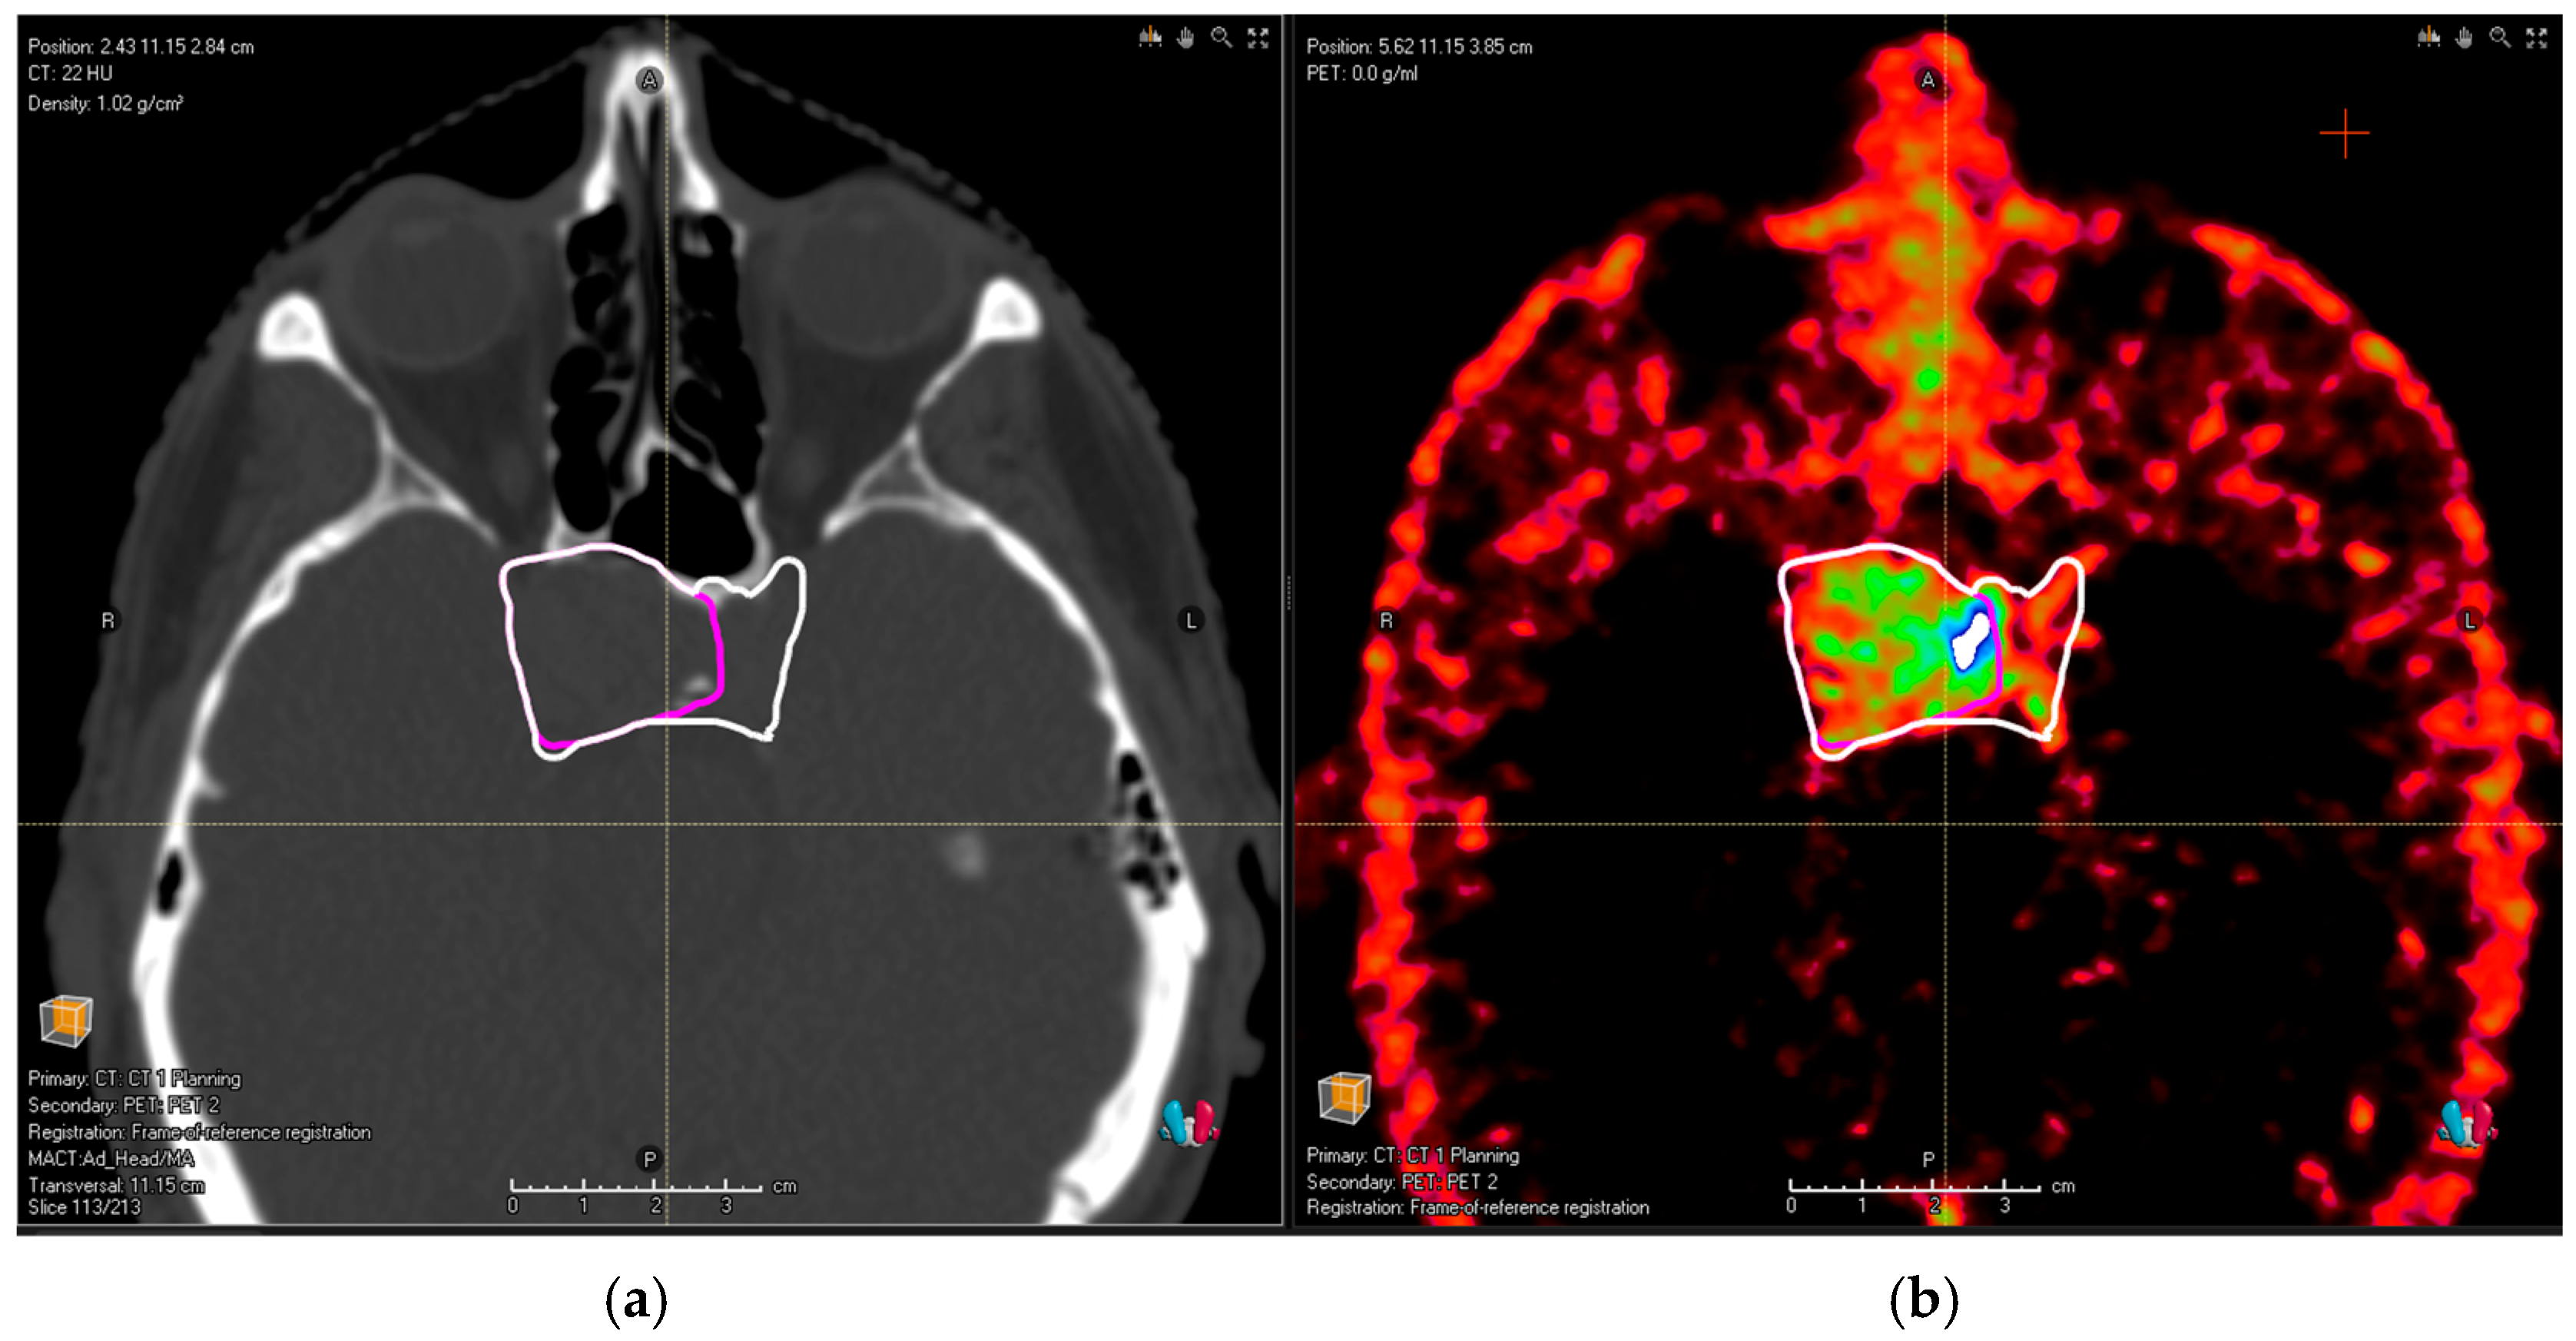

• PitNET with the bilateral involvement of cavernous sinus (as depicted in Figure 1);

Figure 1. (a) Planning the CT image of a patient with pituitary adenoma. Pink contour shows common MRI volume; after the addition of PET/CT, (b) the observers identified an infiltration in the left cavernous sinus (white contour).

In all these cases, the new tumor volume first identified with the aid of DOTA PET/CT should be considered relevant for the proton treatment plan. There was no relevant tumor volume missed by observers in MRI compared to PET/CT for glomus tumors. Figure 1a shows the planning CT image of a patient with pituitary adenoma; Figure 2a shows the planning CT image of a patient with an aggressive pituitary adenoma.